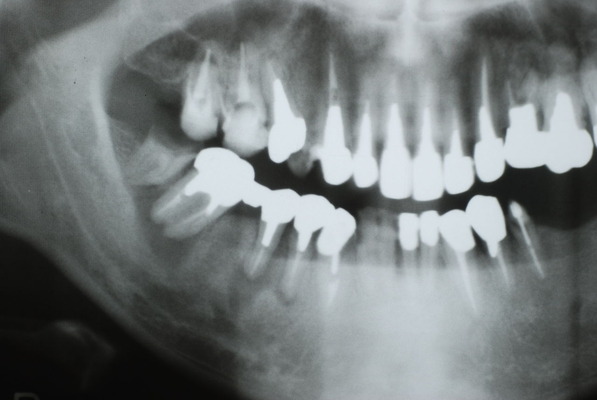

歯周病の疑いで東京のかなり遠方の方が来院されました。

驚くべきことですが、定期検診は受けていたそうです。しかしながら歯周病の指摘は受けたことがないそうです。

何故か?定期検診が虫歯のチェックのみになり、又肝心の歯周病の検査や歯周病の部分の予防や治療のためのブラシの使い方などを学んだ事がないのです。

本当に患者さんのことを考えると憂鬱になります。歯周病が悪化すると殆ど回復は無理だからです。